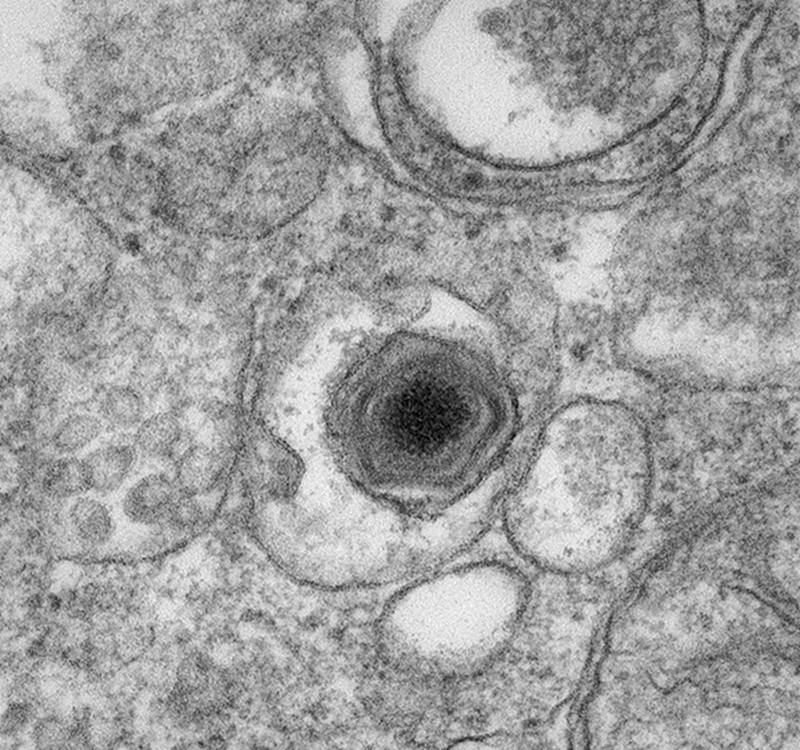

Virus de la peste porcina africana. Ben Clark (Wikimedia Commons)

Diferenciación científica: Gripe vs. Peste Es crucial no confundir este caso con la Peste Porcina Africana (PPA). Según el CSIC, la PPA es un virus de ADN complejo (familia Asfarviridae) que está devastando poblaciones de jabalíes en Cataluña, pero no afecta a los seres humanos. Por el contrario, la Gripe Porcina (H1N1v) es un virus de ARN (familia Orthomyxoviridae) que sí tiene la capacidad de mutar y saltar a las personas. La coincidencia en el tiempo de ambos virus en la misma zona geográfica (Lérida) complica la gestión sanitaria y la percepción de riesgo en el sector ganadero de Mallorca, que teme un endurecimiento de las restricciones comerciales.